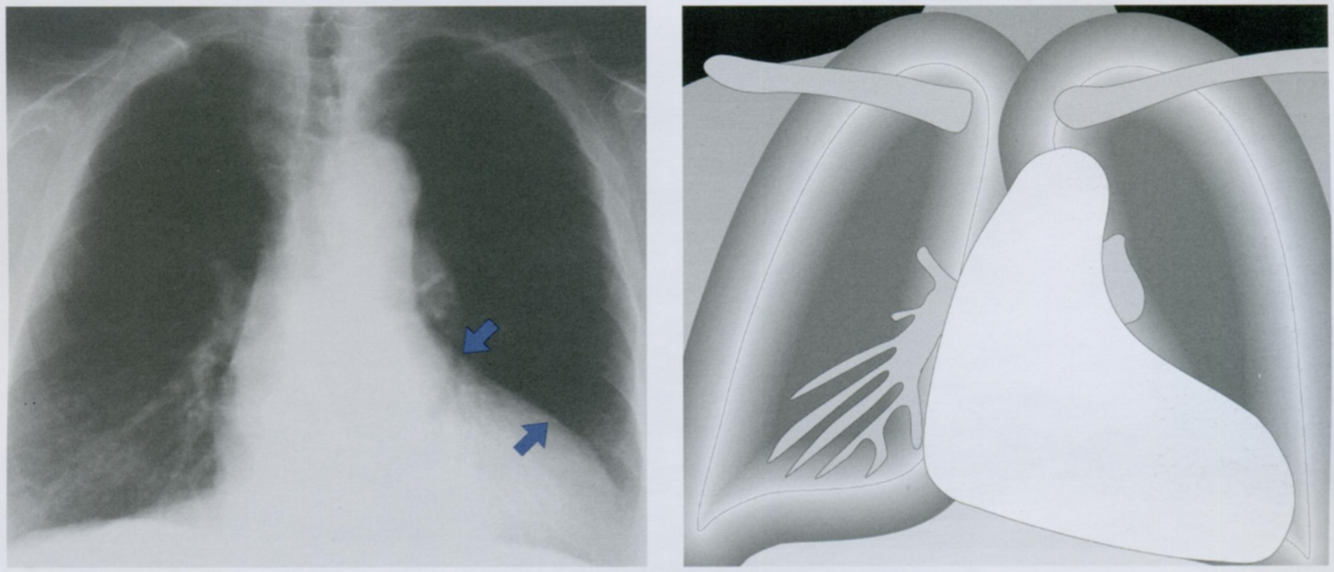

Оцените Rx снимок. Какие признаки трикуспидальной недостаточности Вы видите?

Относительно часто встречается трикуспидальная недостаточность, которая может развиваться, например, при митральном стенозе.

Клапан становится неполноценным из-за миогенной дилатации правого желудочка и кольца трехстворчатого клапана. Дилатация правого предсердия приводит к значительному расширению тени сердца вправо на рентенограмме в ЗПП (стрелки).